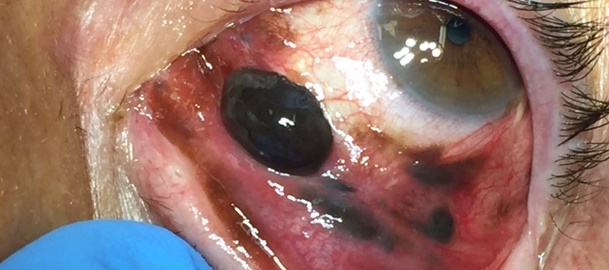

4 Melanoma della congiuntiva

Paziente di 62 anni si reca per visita oculistica per neoformazione e pigmentazione congiuntivale.

Effettuata biopsia congiuntivale dalla quale è emersa la natura della neoformazione cioè un melanoma della congiuntiva.

Sono stati predisposti tutti gli accertamenti per l'inquadramento sistemico della malattia e l'iter terapeutico indicato.